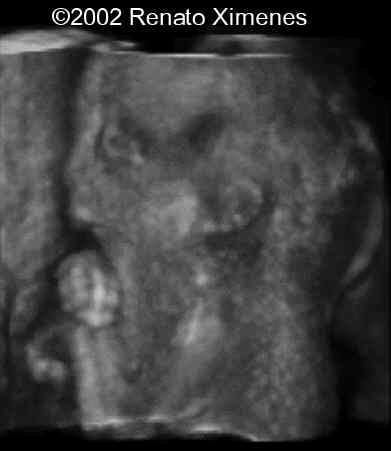

The 3D reconstructions nicely demonstrate the webbing of the neck, low-set ears and micrognathia.

case0072-10

case0072-9